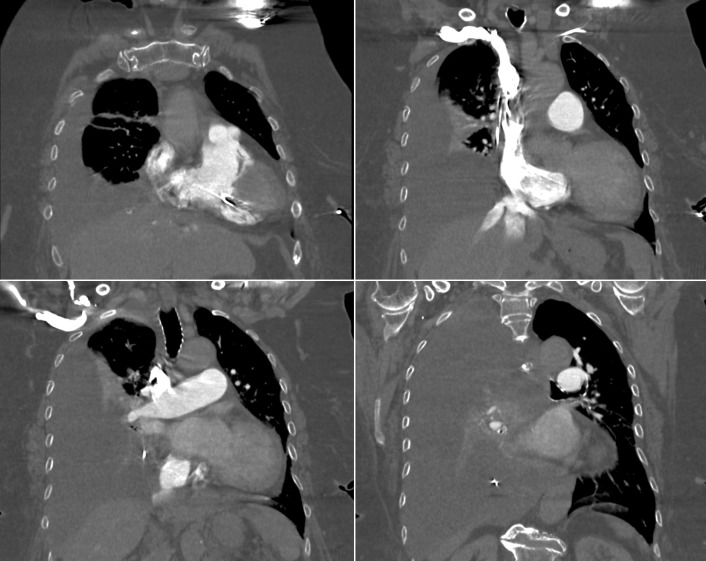

Endocardial Pacer Leads

The position and integrity of endocardial pacer leads should be verified, especially when pacemaker dysfunction is clinically suspected ( Graphics 23-1 to 23-4 ; Figs. 23-1 to 23-15 ).The most common cause of pacemaker dysfunction that is apparent on the chest radiography is distal lead displacement/misplacement.

With a right atrial lead , the tip should be in the right atrial appendage.

With a right ventricular lead , the tip should lie anteriorly at the apex of the heart.